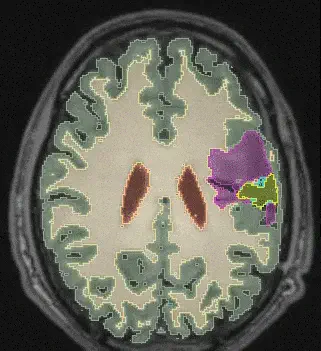

Learning joint Segmentation of Tissues And Brain Lesions (jSTABL) from task-specific hetero-modal domain-shifted datasets Dec 1, 2020 Go to Project Site jSTABL example Tom Vercauteren Professor of Interventional Image Computing Tom’s research interests include machine learning and computer assisted interventions